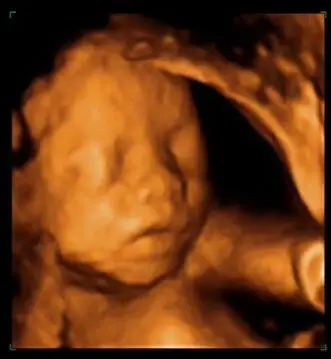

怀孕期 今天去医院做彩超拍到的 麻烦大家帮忙看看是不是男宝 我

> 帖子详情 发帖:1776421 用户:9089966 150*****288_9xmm 孕32周

四维彩超大家能不能看出来男宝还是女宝

最佳!四维单上哪3个亮点能判断胎儿是男孩?